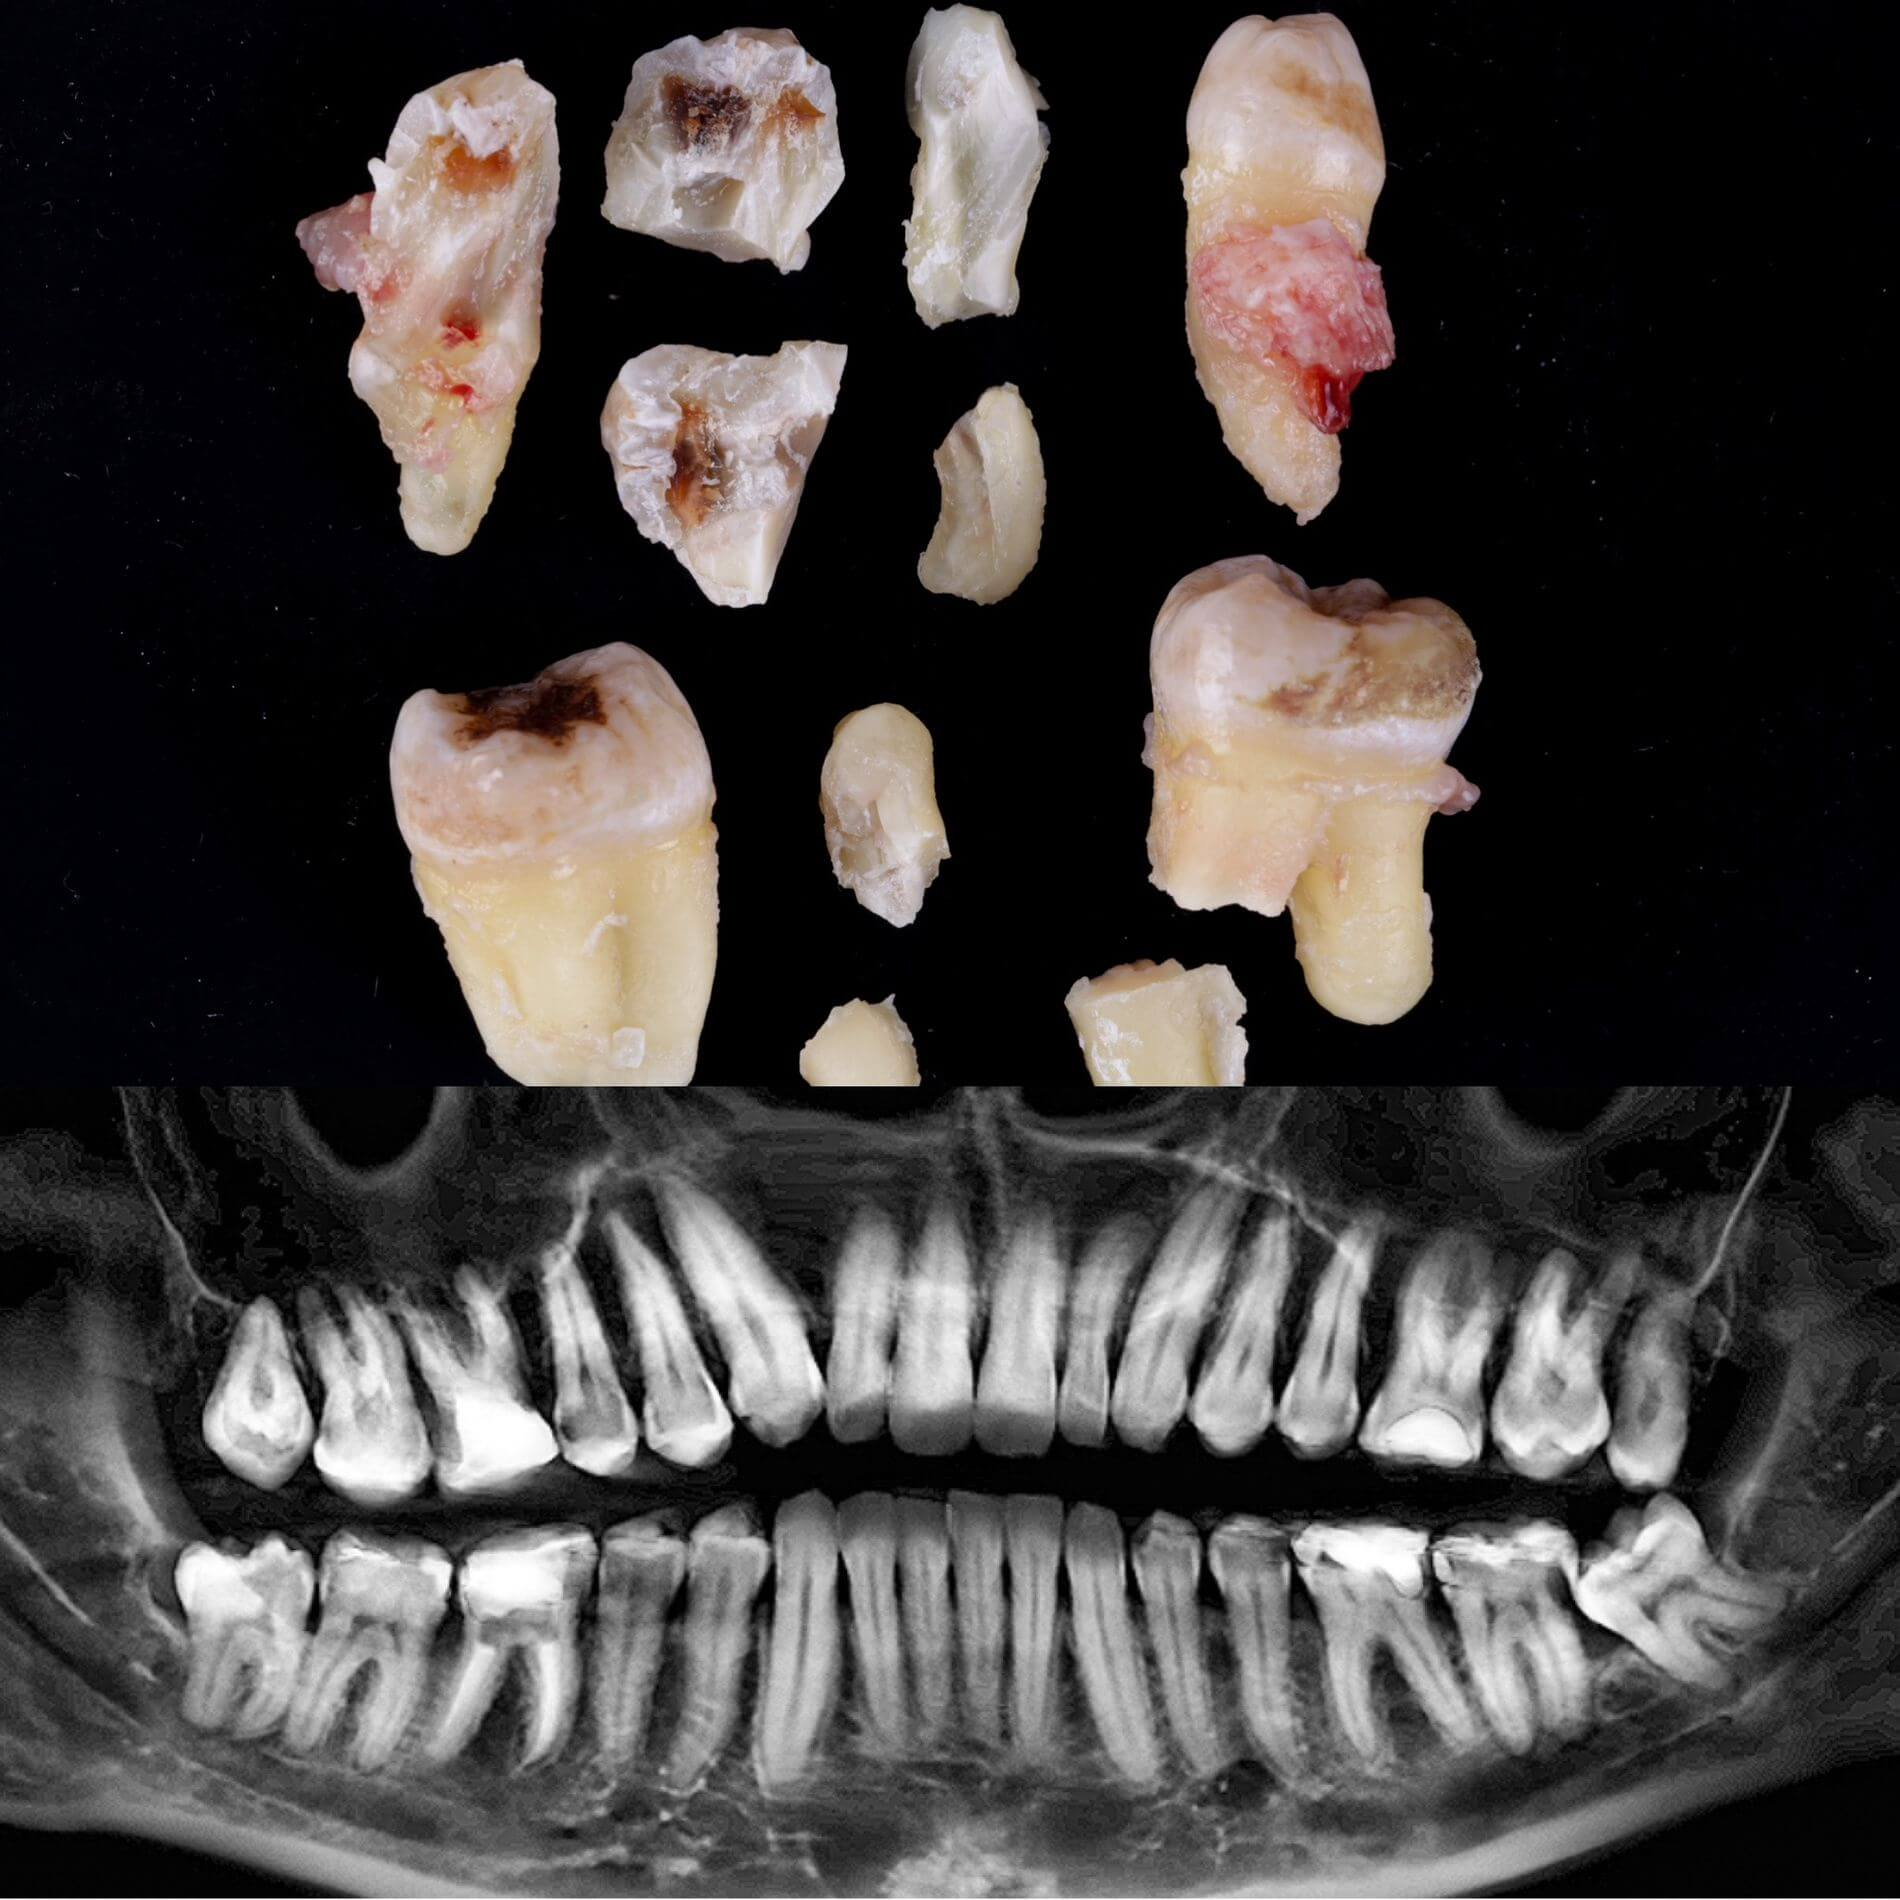

Галерея